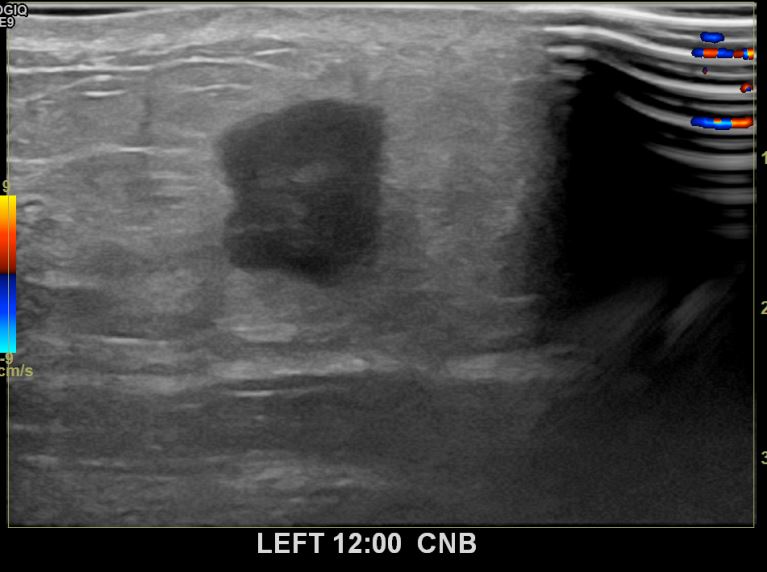

상기환자는 만져지는 좌측멍울로 내원하신 40대중반

여성분으로 의심스러운 좌측혹 조직검사 시행해 침윤성암 으로 진단되었습니다